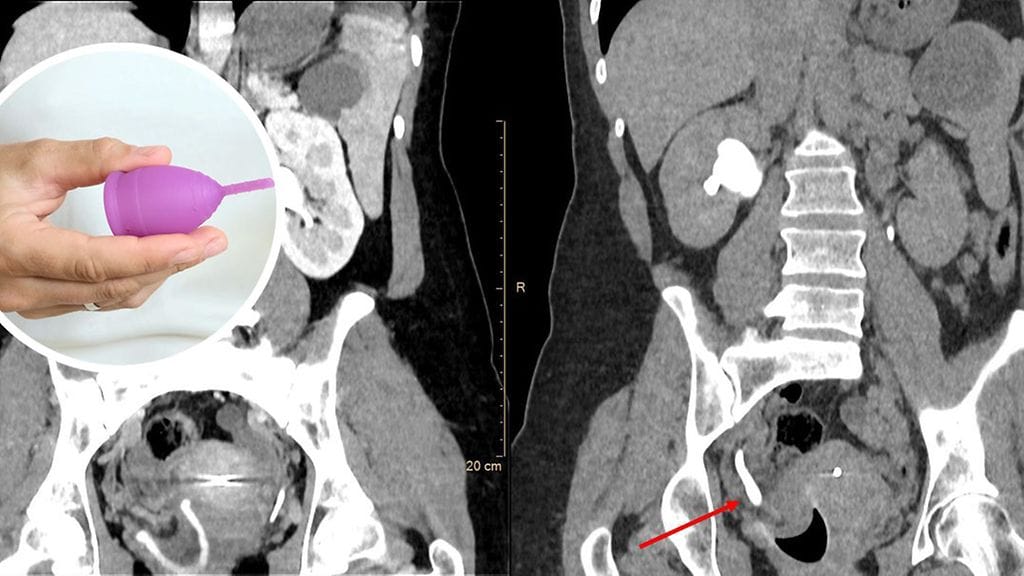

Kuvauksissa paljastui, että kuukuppi oli sijoitettu aivan virtsaputken aukon viereen. Oikea munuainen ja virtsanjohdin olivat turvonneet.

Kuukuppi esti virtsan virtauksen

Naista kehotettiin olemaan käyttämättä kuukuppia seuraavien kuukautisten aikana. Kuukauden kuluttua otetuissa kuvissa turvotus oli laskenut ja virtsaa poistui molemmista munuaisista tavanomaisesti.